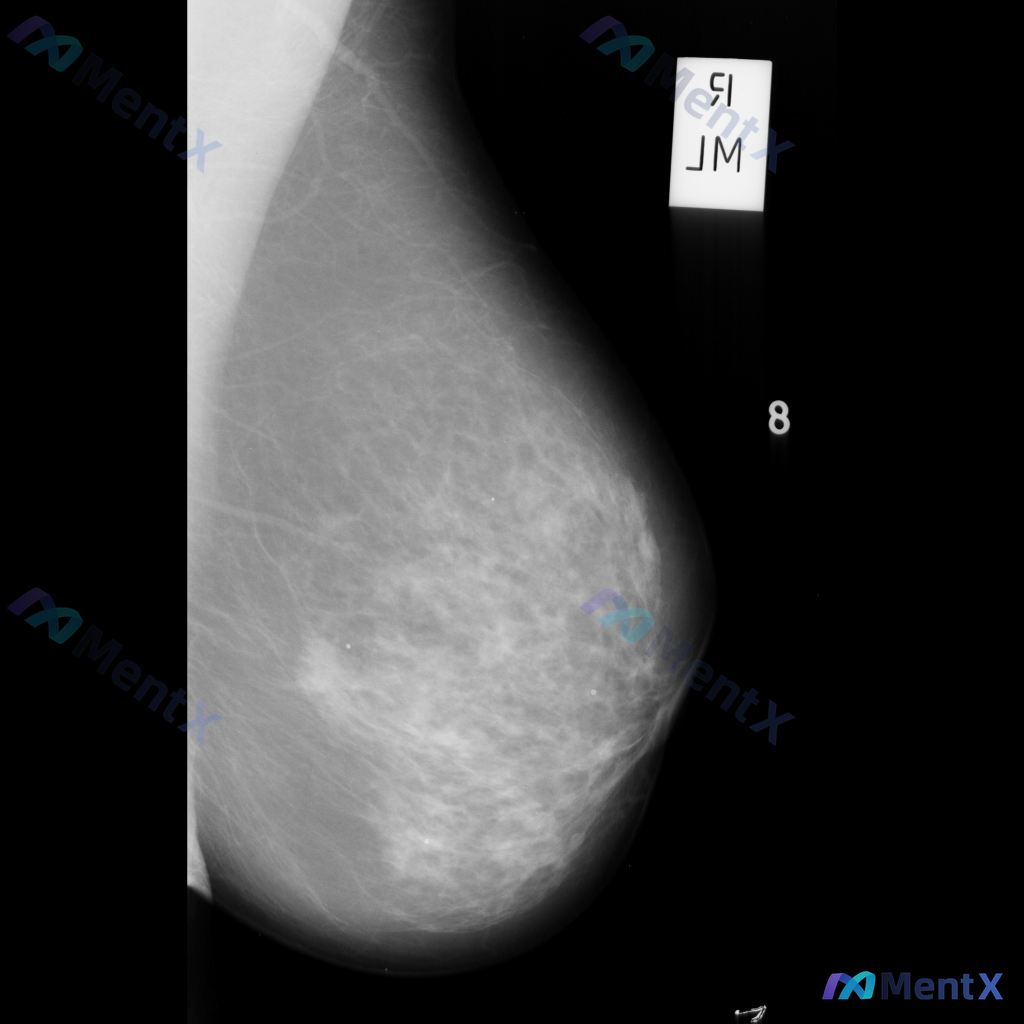

整理到一张乳腺钼靶影像的描述资料,想请大家帮忙看看更倾向哪种情况。 【基本影像背景】 - 检查侧:右侧乳腺 - 乳腺构成:不均匀致密型(BI-RADS C型) 【影像异常发现】 - 右侧乳腺见一处不规则形高密度肿块 - 肿块边缘呈毛刺状或星芒状 - 局部伴有显著的结构扭曲 - 无明确钙化灶显示 -...

整理到一张乳腺钼靶影像资料,影像所见:左乳中上象限可见不规则高密度致密影,边界部分模糊或伴毛刺状改变,局部乳腺组织结构可见轻度扭曲。 想和大家讨论一下:单看这张影像的异常表现,你认为用哪个术语描述最贴切?

整理到一张乳腺钼靶影像的读片资料,想和大家讨论一下。 影像显示:左乳下象限可见一个不规则形、高密度的肿块,边缘模糊且部分区域有毛刺样改变;肿块区域内有散在分布的微小多形性钙化点,呈簇状分布;肿块周围还可见乳腺腺体结构紊乱和牵拉。 目前没有提供患者的既往病史、临床症状或其他检查结果。 单看这张影像的异...